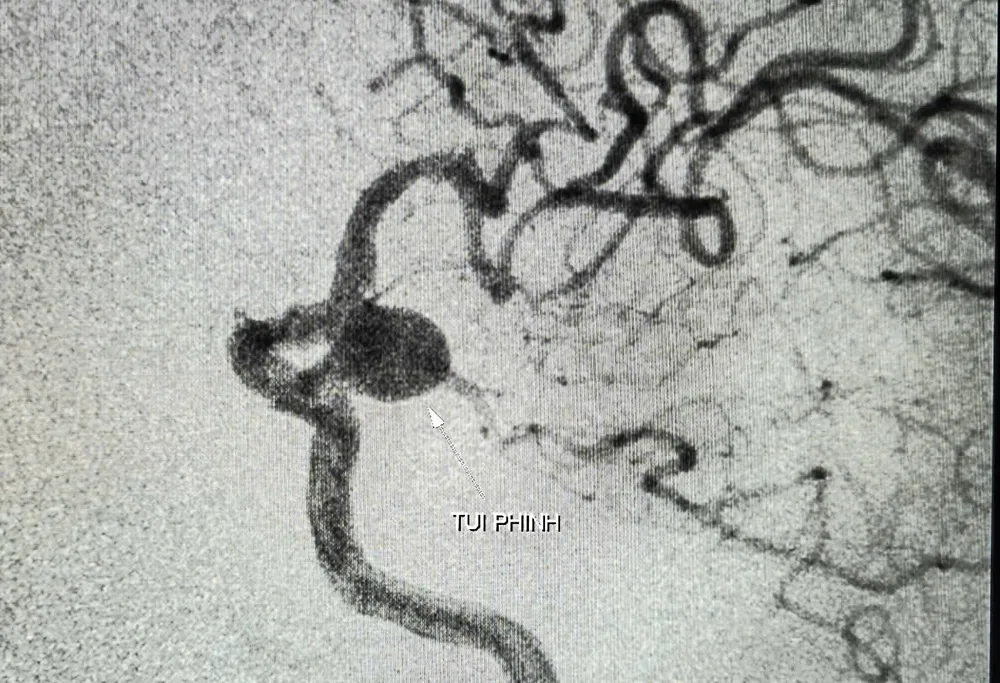

Túi phình mạch não (kích thước lớn) được phát hiện ở cụ bà 90 tuổi

Kết quả chụp cắt lớp vi tính và cộng hưởng từ cho thấy bệnh nhân bị nhiều tổn thương vùng não, túi phình đoạn gốc động mạch cảnh trong - thông sau bên trái, kích thước 9,2x12mm, nguy cơ vỡ cao.